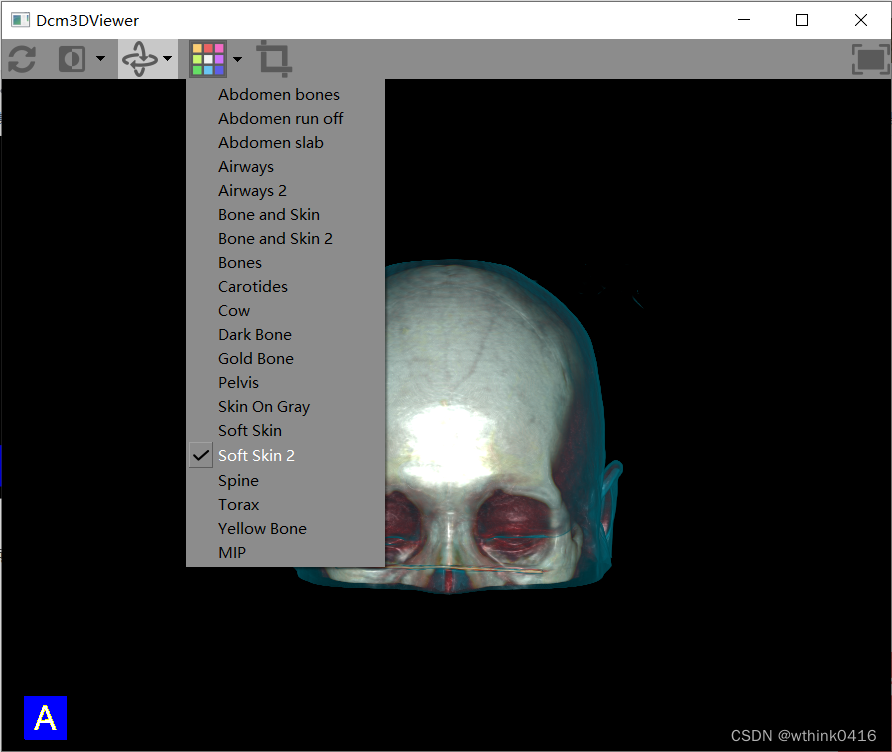

15、点击![]() 伪彩图标,可实现不同的显示效果。

伪彩图标,可实现不同的显示效果。